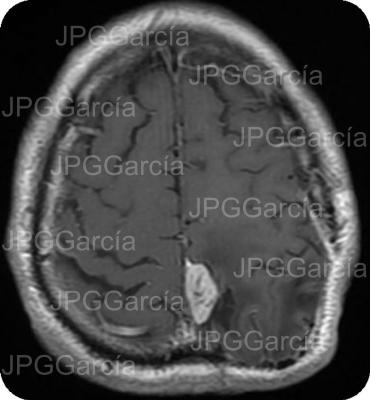

Tumor del plano esfenoidal clasificado por imagen como Meningioma visto a través de resonancia magnética cortes axial y coronal